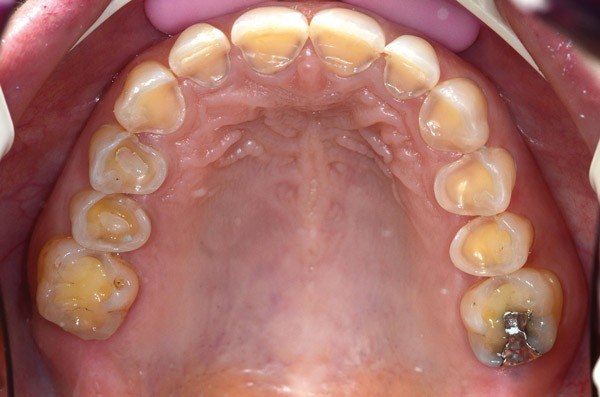

À l’examen clinique (fig. 2 à 4), on observe :

– l’absence de 17, 27 et 47 (suite de lésions carieuses volumineuses) ;

– un parodonte sain ;

– des érosions sévères généralisées, symétriques et bilatérales (occlusales, palatines et vestibulaires au maxillaire) ;

– des lésions carieuses débutantes de site 3 ;

– des obturations préexistantes infiltrées ;

– une vitalité pulpaire conservée sauf au niveau des prémolaires maxillaires ;

– une usure des bords libres des incisives mandibulaires